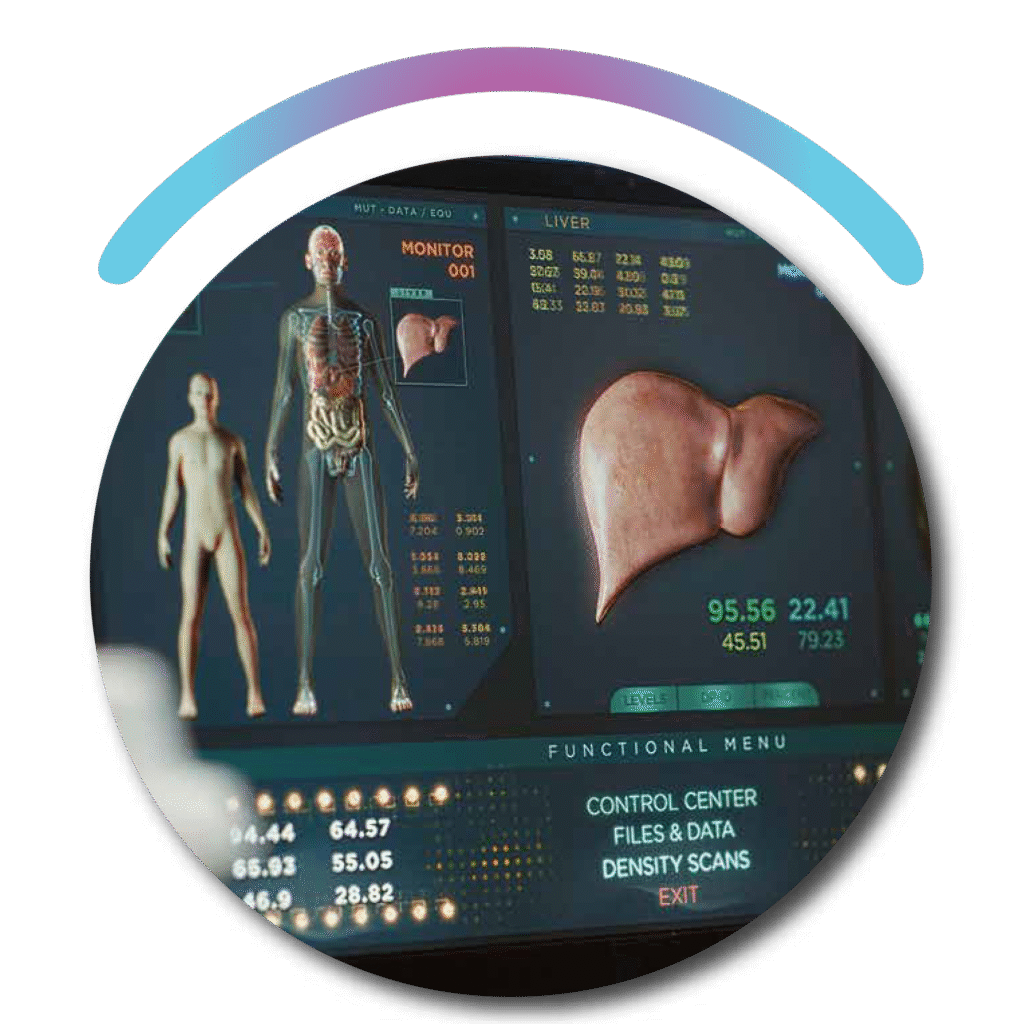

LIVER TRANSPLANTATION SIMULATION

Our Liver Transplantation Simulation uses advanced AI to model and plan complex transplant procedures with precision. It assists surgeons in visualizing anatomical structures, assessing graft compatibility, and optimizing surgical outcomes. By enhancing preoperative planning, it reduces risks and improves success rates in liver transplantation.